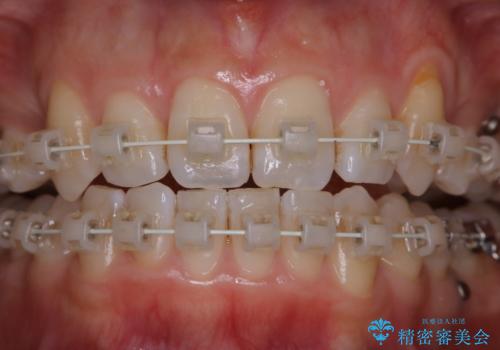

ワイヤー矯正中のPMTC

- ワイヤー矯正中に装置の周りの着色が気になるとのことで来院されました。PMTC30分コースを行いました。

ワイヤー矯正中も、歯の表面に着色(ステイン)が付着することがあります。着色(ステイン)が付着したままだと審美的な問題以外にも、虫歯を発見しずらいことや、細菌が繫殖しやすくなることがあります。クリーニングを行うことで、虫歯や歯周病予防に効果的だったり、もちろん見た目も審美的です。クリーニング後には、汚れが取り除かれ、お口の中がスッキリ・爽快感で気持ちがよくなります。矯正中も定期的にPMTCを行うことが大切です。